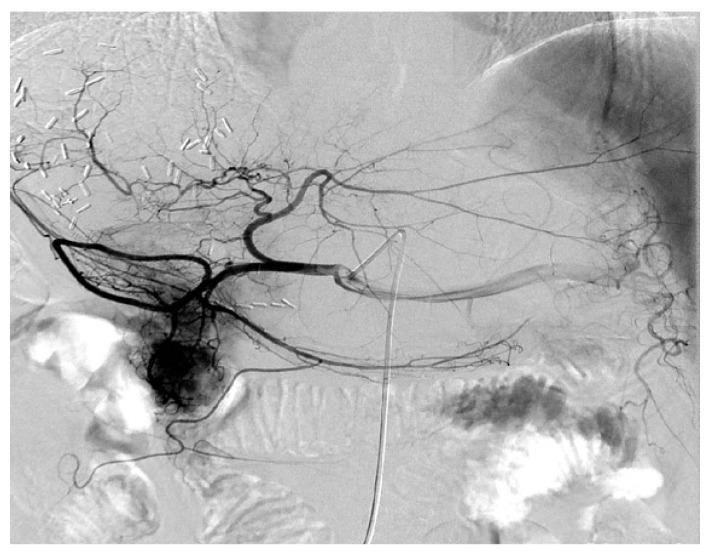

There is no information regarding transarterial chemoembolization (TACE) as a postoperative management after hepatic resection for patients with hepatitis B virus (HBV)-associated intrahepatic cholangiocarcinoma (ICC). Forty-two patients with pathological confirmation of HBV-associated ICC were enrolled. Prognostic impact of the clinicopathological factors as well as postoperative TACE were evaluated. Computed tomography findings of HBV-associated ICC were assessed. Tumor size of larger than 5 cm (hazard ratio [HR], 5.654; 95% confidence interval [CI], 1.175 to 27.204; P = 0.031), postoperative TACE (HR, 0.123; 95% CI, 0.023 to 0.643; P = 0.013), and lymph node metastasis (HR, 3.284; 95% CI, 1.236 to 8.724; P = 0.017) revealed to be independently associated with survival outcomes of patients with HBV-associated ICC. Application of TACE, as a postoperative management to control early local recurrence on the basis of hepatic arterial phase enhancement, significantly prolonged survival outcomes (1-yr, 88.9%; 3-yr, 77.8%; 5-yr, 66.7%), compared to the patients who did not receive TACE (1-yr, 63.6%; 3-yr, 30.8%; 5-yr, 13.0%). When analyzed according to the status of hepatic arterial phase, arterial phase enhancement demonstrated a favorable trend on prognosis of patients with HBV-associated ICC without statistical significance (HR, 0.435; 95% CI, 0.140 to 1.359; P = 0.141), and TACE independently improved overall survival of patients with arterial phase enhancement (HR, 0.105; 95% CI, 0.014 to 0.774; P = 0.027). Put together, our results indicate that postoperative TACE effectively improves prognosis of HBV-associated ICC with arterial phase enhancement in CT scans. Large-sized trials are required for our results to be applied in clinical medicine.

目前尚无关于经肝动脉化疗栓塞术(TACE)作为乙型肝炎病毒(HBV)相关肝内胆管细胞癌(ICC)患者肝切除术后管理的信息。本研究共纳入 42 例经病理证实的 HBV 相关 ICC 患者。评估了临床病理因素以及术后 TACE 的预后影响。评估了 HBV 相关 ICC 的 CT 表现。肿瘤直径大于 5cm(风险比[HR],5.654;95%置信区间[CI],1.175 至 27.204;P=0.031)、术后 TACE(HR,0.123;95%CI,0.023 至 0.643;P=0.013)和淋巴结转移(HR,3.284;95%CI,1.236 至 8.724;P=0.017)是与 HBV 相关 ICC 患者生存结果独立相关的因素。基于肝动脉期增强,TACE 作为一种术后管理方法,用于控制早期局部复发,与未接受 TACE 的患者相比,显著延长了生存结果(1 年,88.9%;3 年,77.8%;5 年,66.7%)(1 年,63.6%;3 年,30.8%;5 年,13.0%)。根据肝动脉期的状态进行分析时,动脉期增强显示出对 HBV 相关 ICC 患者预后的有利趋势,但无统计学意义(HR,0.435;95%CI,0.140 至 1.359;P=0.141),TACE 独立改善了动脉期增强患者的总生存(HR,0.105;95%CI,0.014 至 0.774;P=0.027)。综上所述,我们的研究结果表明,术后 TACE 可有效改善 CT 扫描显示动脉期增强的 HBV 相关 ICC 的预后。需要进行大型临床试验,以便将我们的研究结果应用于临床医学。